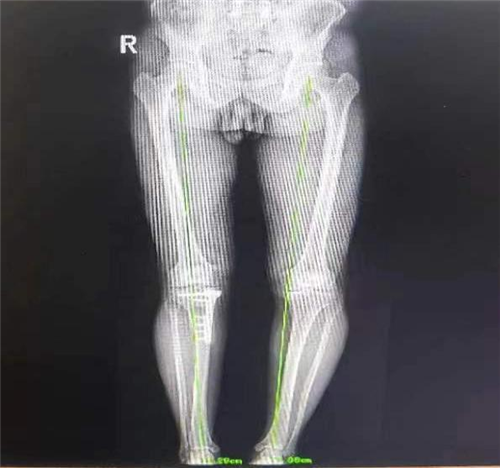

而近期患者感觉其左膝关节疼痛逐渐加重,伴随肿胀,甚至需要扶拐前行。因为患者对第一次手术效果非常满意,所以再次来到我院骨一科就诊。李强主任团队针对患者具体病情进行评估,发现患者负重位X线片显示左膝关节内侧间隙变窄,胫骨内翻,胫骨近端后倾角 76°,胫骨近端内侧角小于82°,左膝关节退行性改变。外侧间室及外侧关节间隙相对完好,测量后发现其畸形主要为关节内翻畸形。